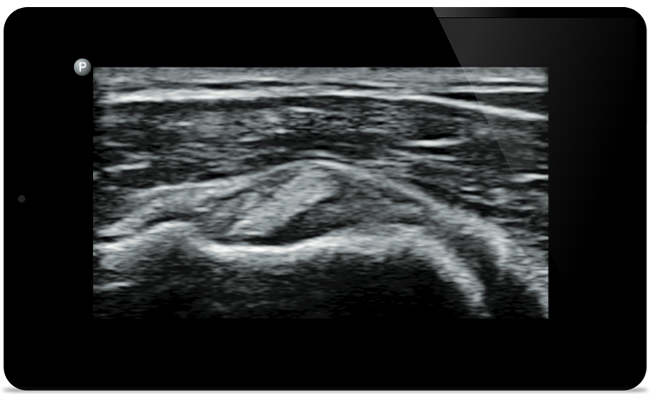

Lumify can help you assess patients from head to toe, whether it’s plantar fasciitis, tendonitis or bursitis in the patellar tendon, or even shoulder instability in the rotator cuff.

Get the full picture with clear whole-body imagery for a fast, accurate response during MSK examinations.

Padstatic case example image

See more when it counts

From revealing the subtle details of an image to uncovering enriched tissue definition from multiple angles, Lumify can help you make real-time decisions with more confidence from assessment through recovery.